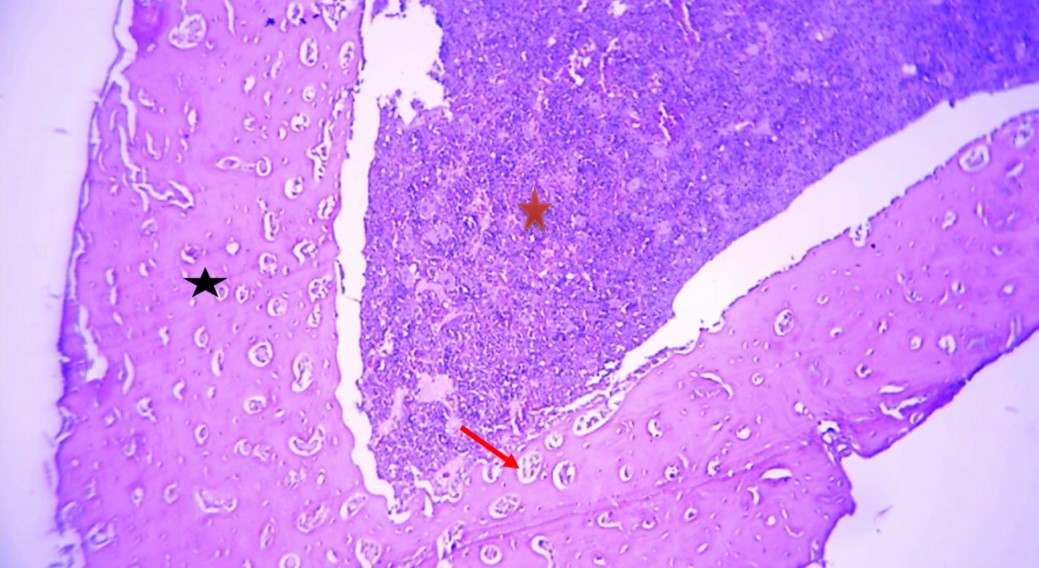

as shown Histologic al alterations in femur bone in rats with zinc deficiency in (Fig 2), involved loss of trabecular mass especially compact bone and altered osteoclast activity in the bone tissue were evaluated by atrophy in osteoblast and then decrease in bone density as compared to femur bone in rats without zinc deficiency in (Fig1) which characterized by normal architecture bone tissue showing normal compact (black star), spongy bone(black arrow) normal osteoblast (red arrow), osteoclast(yellow arrow) and normal trabecular (green arrow). Whereas the administration of zinc and Vit D cause to restoration these histological changes which including significantly improve in the trabecular mass (compact and spongy bones), improve bone density as well improve tissue remodeling and semi normal trabecular mass with normally distribution of osteoblast and osteoclast (red arrow) with good appearance of compact and spongy bone as shown in (Figs 3 and 4), the above changes in femur bone as comparison to femur bone in (Fig 2).

Figure (2).